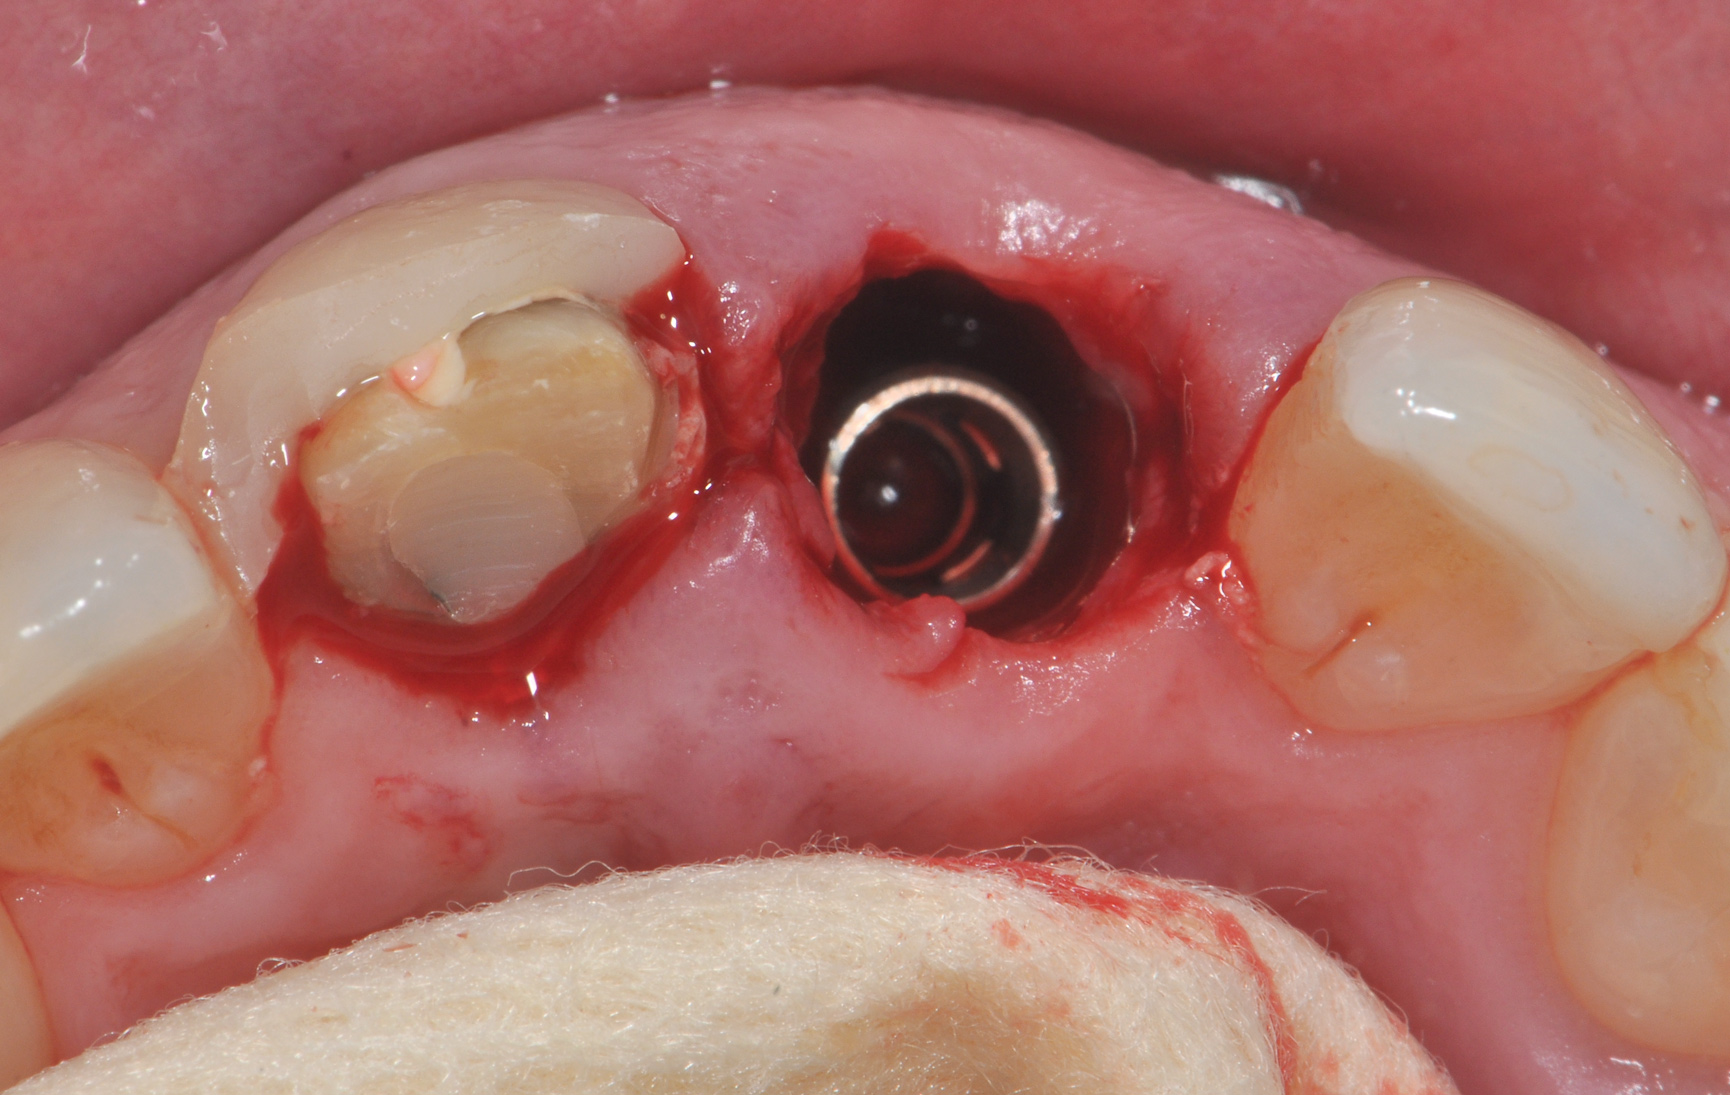

Fig 6. The 3-mm buccal gap was grafted tightly with low-substitution DBBM, and a pouch was created as a mini full-thickness flap to accept a connective tissue graft.

Figure 6

The patient, a healthy 45-year-old nonsmoking woman (American Society of Anesthesiologists [ASA] II), presented with a failed maxillary central incisor due to severe internal-external root resorption (Figure 1). She had a high esthetic risk profile based on 12 presenting esthetic risk factors (key No. 1), including a high lip line, high esthetic expectations, and adjacent teeth that had been restored (Figure 2).Site-specific CBCT (Carestream CS 9300, Carestream Dental, carestream.com) noted a thick intact buccal plate and a class 1 sagittal root position (Figure 3 and Figure 4). Preplanning with a bone-level 4.1-mm diameter x 14-mm long implant (Straumann Bone Level Roxolid® SLActive, Straumann, straumann.com) assured a 3-mm buccal gap upon placement and a screw-retained position (key No. 2). Prior to placement, intact buccal and palatal walls were confirmed. Figure 5 shows palatal wall placement of the implant after minimally traumatic flapless tooth extraction. An anatomically correct surgical guide template was used to assure a screw-retained position and correct vertical depth of approximately 4 mm from the mid-buccal apical extent of the guide template, which correlated to 1 mm apical of the intact buccal plate (key Nos. 3 through 5). The two-unit (8-9x cantilever) fixed provisional was recemented post-surgery. The 3-mm buccal gap was grafted tightly with a low-substitution DBBM (Bio-Oss®, Geistlich Pharma, geistlich-na.com) (key No. 6), and a pouch was created with a Buser membrane instrument (Hu-Friedy, hu-friedy.com) from line angle to line angle as a mini full-thickness flap to the mucogingival border to accept a connective tissue graft (Figure 6). The connective tissue graft, 1-mm thick x 12-mm long x 7-mm wide (Figure 7), was harvested from the palate (key No. 7).